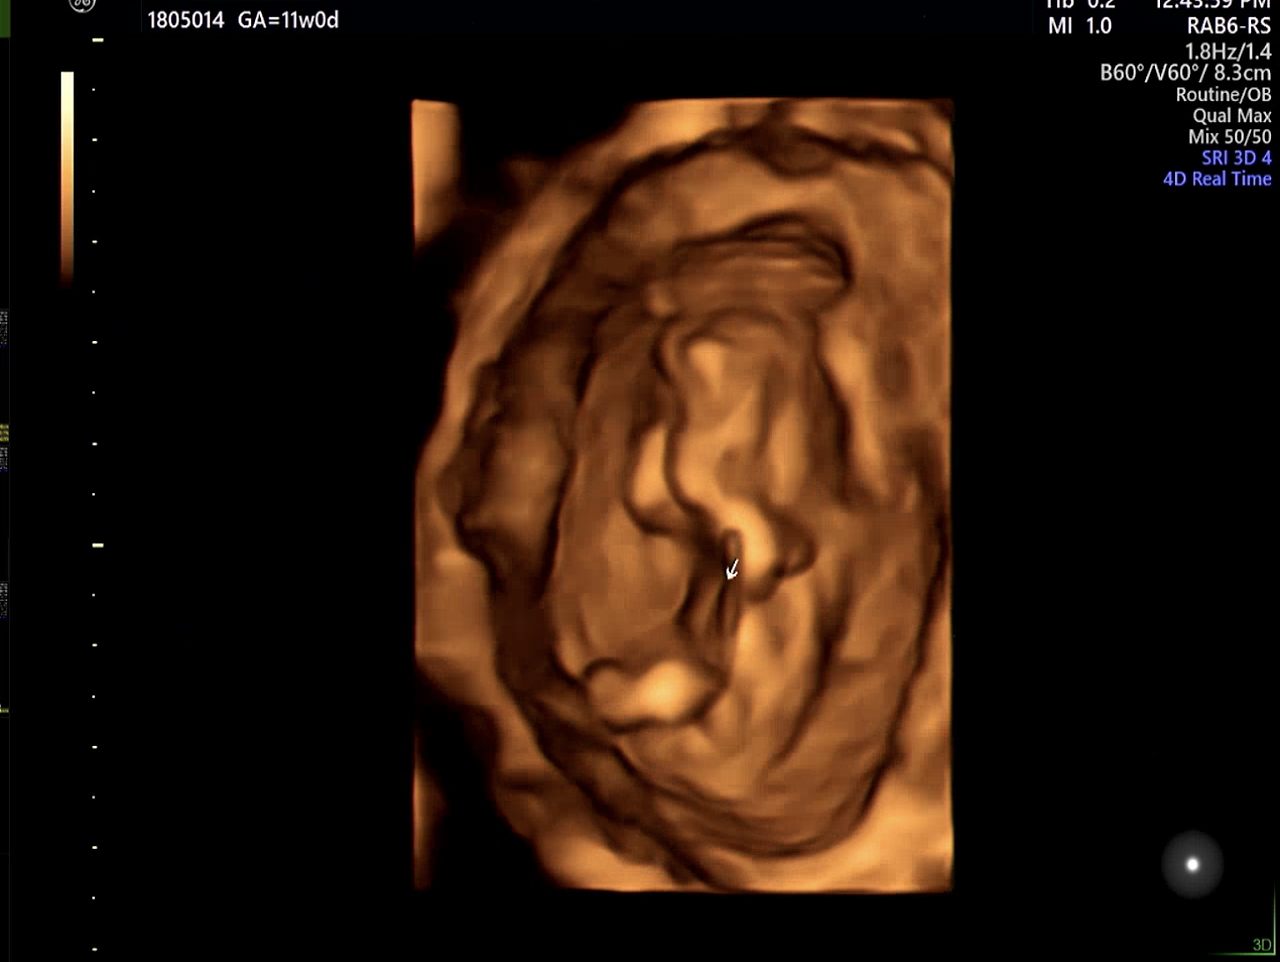

아기집을 확인하고 나니 비로소 실감이 난다.

두손으로 얼굴을 가리고 있어서 얼굴은 아직 못봤지만 다음주 정기검진때는 얼굴을 볼 수 있길 기대해본다.